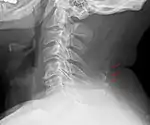

Neck

Bone tissue in the nuchal ligament.